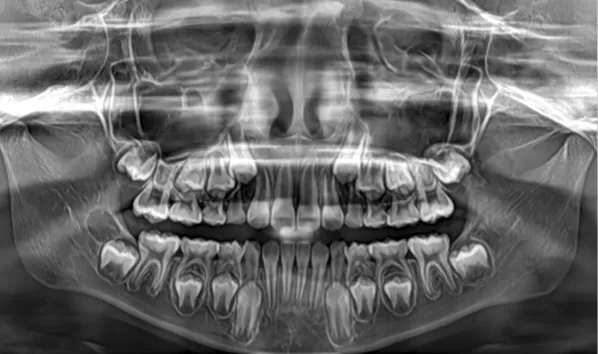

X-rays before treatment

[Panoramic Radiography/Lateral Cephalogram]